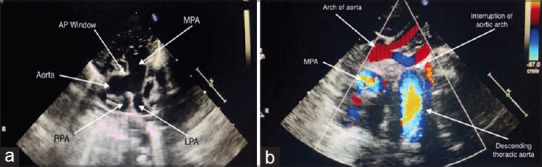

Berry et al. (1982) described a rare syndrome associated with distal aortopulmonary window, aortic origin of the right pulmonary artery, intact ventricular septum, and interruption or coarctation of the aorta. Here, we present the first neonatal case of single-stage repair of Berry syndrome in India. Timely surgery and skilled postoperative care define the short-term and long-term outcomes. Single-staged repair is preferred wherever feasible.